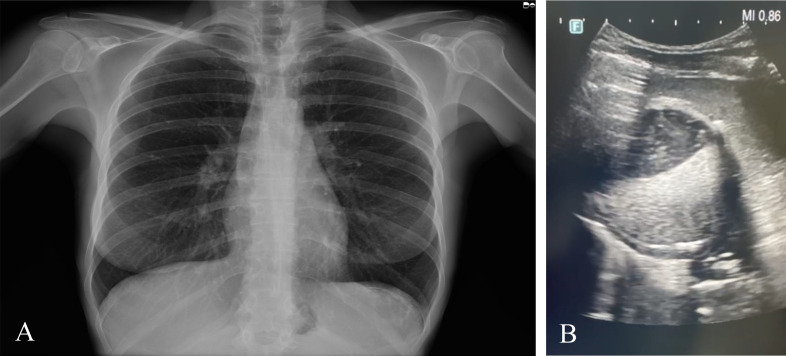

Cystic echinococcosis (CE) is a zoonotic disease caused by Echinococcus granulosus sensu lato, the metacestode of a tapeworm parasite of high medical importance. Infection of the parasite leads to the development of echinococcal cysts, and the spleen is a rarely infected organ. A 46-year-old woman who was born and who resides in Sardinia, Italy, was referred to the Echinococcosis outpatient clinic at the University Hospital of Sassari (Sardinia, Italy) for a pain in the left flank. She used to live in the countryside, in contact with several animals, and for 2 years, she had been working in a family garden, growing vegetables as a hobby. Ultrasounds and X-ray were performed, which evidenced a rounded formation in the upper third of the spleen, while a CT scan confirmed a parasitological cyst. Immunological examinations on serum samples did not detect specific antibodies against Echinococcus spp. Following surgical exportation, the whole spleen with the cystic lesion was delivered to the World Organisation for Animal Health (WOAH) and the National Reference Laboratory for Echinococcosis for further laboratory analyses. Moreover, characterization of the cyst fluid resulted dense and shiny. Observation under a light microscope at ×400 magnification revealed the formation of rectangular crystals and aggregates attributable to cholesterol molecules. Subsequently, through parasitological investigation, molecular biology investigations confirmed E. granulosus sensu stricto G1. We describe cholesterol crystals in a splenic echinococcal cyst for the first time. There is no clear explanation of how the cholesterol crystals formed in this case, but this was attributed to multifactorial causes, including atherosclerosis, chronic inflammation, parasite metabolism, and host responses.